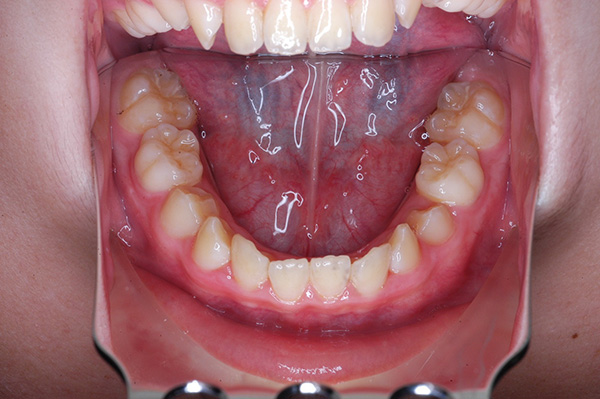

| 口腔内所見 | over jet 5.5mm,over bite 5.0mm,大臼歯関係はⅠ級 、Hellmanのdental ageはⅢBであり上突歯列を呈していた。 |

| パノラマ所見 | 上顎左右側犬歯は近心傾斜し側切歯歯根に重なるように認められた。 |